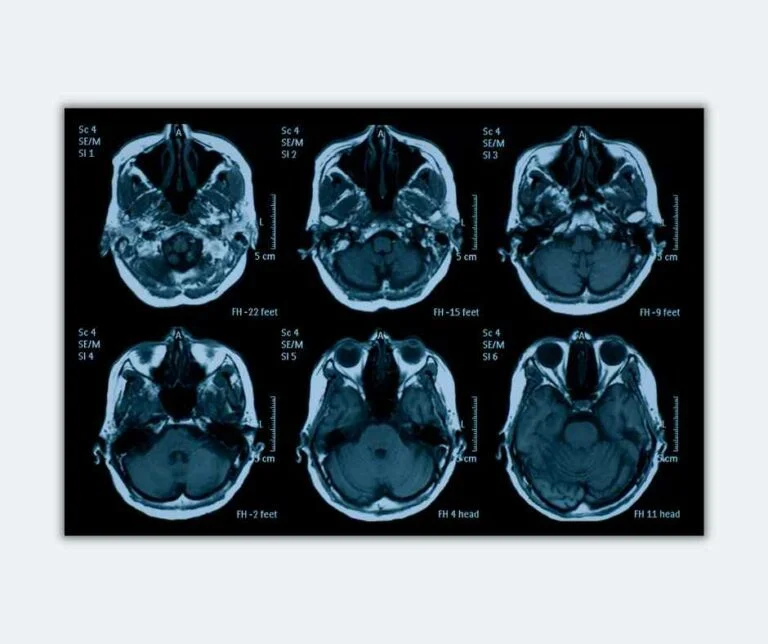

A quick note: almost all these studies utilize brain imaging techniques to collect data (for example, fMRIs). We won’t get into those technical details below. Just know these are procedures that allow the researchers to take pictures of the brain and understand brain activity and chemistry.